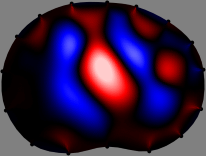

Figs. 3 and 4 compare the performance of the proposed FER method in (20) with the standard regularized least-squares method ((19) when \mathcal{R} is the identity matrix). The regularization parameter of the standard method was heuristically chosen for its best performance, and the parameter of the FER method was set to be one of three different values λ=0.05,0.2,𝜆0.050.2\lambda=0.05,0.2,\infty. The injection current was 1 mARMSRMS{}_{\tiny{\mbox{RMS}}} at 100 kHz, and the frame rate was 9 frames per second. The reference frame at t0subscript𝑡0t_{0} was obtained from the maximum expiration state. The measured data, 𝐕˙(tm)˙𝐕subscript𝑡𝑚\dot{\mathbf{V}}(t_{m}), represent the voltage differences between each time tmsubscript𝑡𝑚t_{m} and t0subscript𝑡0t_{0}. The blue regions, which denote where conductivity decreased by inhaled air, increased during inspiration and decreased during expiration. The FER method with λ=𝜆\lambda=\infty was clearly more robust than the standard method that produced more artifacts originated from the inversion process.

Figure 3: The reconstructed images of the conductivity change of the subject A by the standard regularized least square method and the proposed fidelity-embedded regularization (FER) method for three difference values λ=0.05,0.2,𝜆0.050.2\lambda=0.05,0.2,\infty. Here, the time step is 0.22 seconds (tm+2tm0.22subscript𝑡𝑚2subscript𝑡𝑚0.22t_{m+2}-t_{m}\approx 0.22).